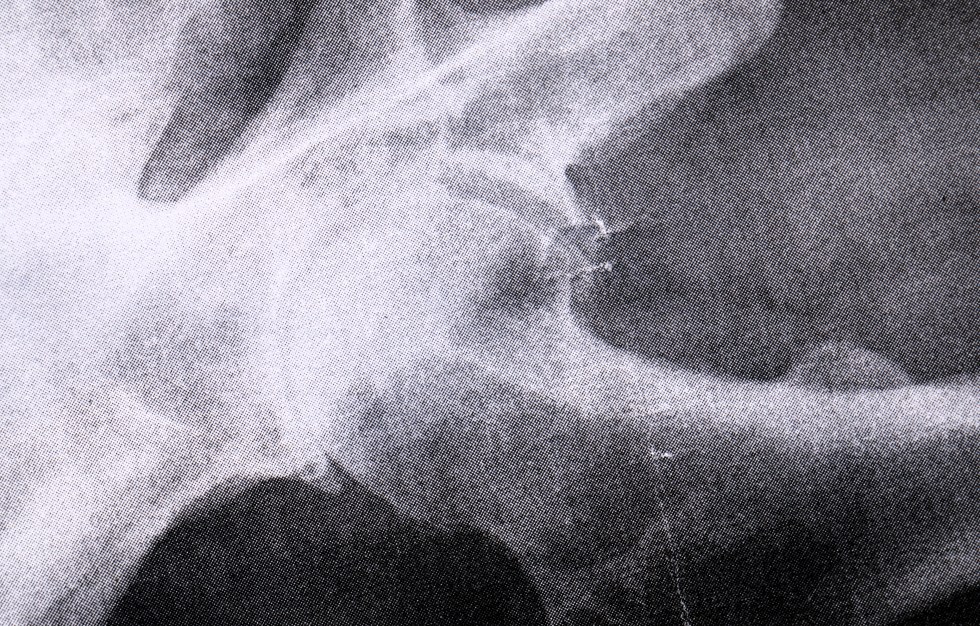

You wake like the man who fell to earth but you won’t feel too bad, that comes a day or so later. And that’s what the Percocet is for. OTOH my right hip joint has been sliding like a strike-slip fault trending toward subduction for years, and that bone-deep ache will be gone forever in that hip joint.

So I can deduct 2 lbs for the new joint, which looks just like one from a Terminator. And never no airport metal detectors for me henceforth. So I’m hopeful these are my last hours walking like Doyle Lonnegan and Richard III.